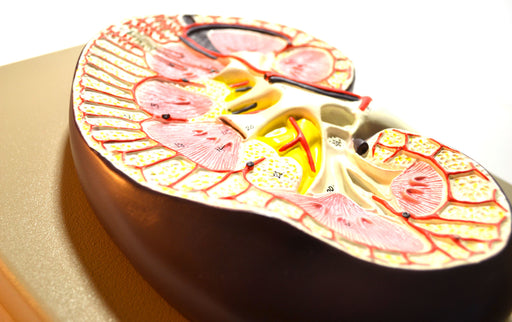

Human Kidney Cross Section Model - 3X Life Size

3x life size (9" X 6.5" X 3") 3D cross section connected to base Detailed Internal Anatomy (cortex, medula, pelvis of ureter, ureter, nephron (Hen...

View full detailsAM0106 -